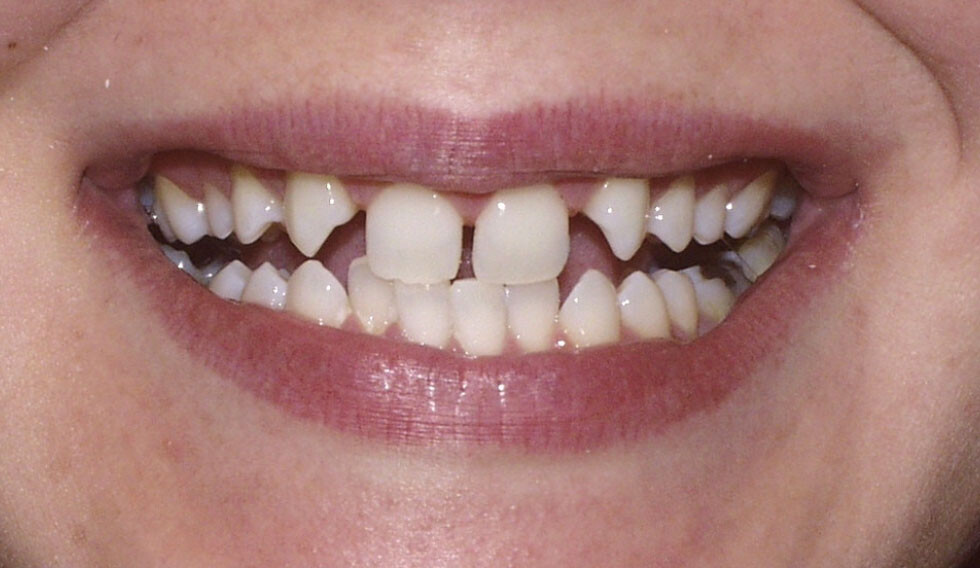

What Are Congenitally Missing Teeth

Congenitally missing teeth or hypodontia is a condition where some of the adult teeth do not develop. Although it can also affect the primary teeth, this is quite rare, unless there is an underlying genetic disorder.

What teeth are usually affected?

Third molars (wisdom teeth) are the most commonly missing but are not included in the definition of hypodontia. This is because it is considered a variation of normal to have missing wisdom teeth. The other most commonly missing teeth are lower second premolars and the upper lateral incisors.

How will I know if I have missing teeth?

Your dental professional will be able to tell if you have any missing teeth. Usually, they will need an x-ray to confirm this. Gaps between your teeth, losing a baby tooth with no adult tooth taking its place or having a baby tooth longer than normal are all signs of having congenitally missing teeth.